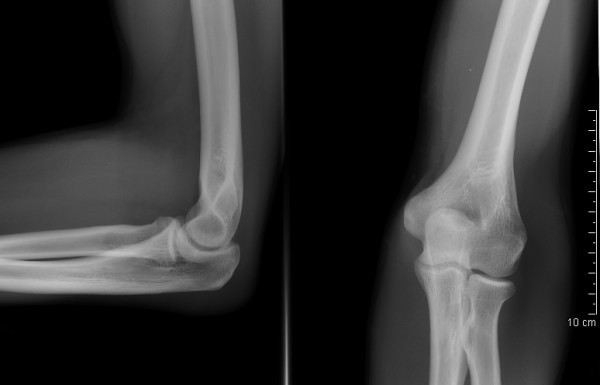

При осмотре ориентируйтесь на полный объем движения до 140-150 при активной работе руки без компенсаторных смещения в соседних суставах. Такой диапазон врач принимает первым при объективное обследование пациента, когда кисть и запястья удерживают нейтральное положение, а плечо не уходит во внешней ротации. На моей практике я часто вижу, что снижение показателя ниже 130 при сохранной функции захвата и отсутствии разрыва связки указывает не на повреждение кость, а на влияние среды, перенесенные нагрузки или желтые факторы анамнез, включая личностные реакции пациентов и страх боли.

Для точного определения допустимых значений врач учитывает возраст, пол, доминирующую руку и данные специальных тесты, которые дополняют скрининговый процесс:

• оценка в положении супинации и при разгибании для исключения влияния лучевого и срединного нерва;

• контроль удержания ключа пальцами и способности сжимать предмет для анализа функции межкостных мышц;

• сравнение с противоположной стороной при подозрении на нестабильность или смещения в пястно-фаланговом и лучезапястного узлах;

• применение проб watson, finkelstein, финкельштейна и ochsner при вопросы про состояние ладьевидного и ладьевидно-полулунного комплекса.